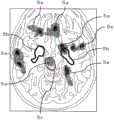

在图4的显示区域41中,脑的切片图像可隔开规定间隔而排列显示。此外,“灰质”的Z评分(数学式1)的分布(Z评分图)可重叠地显示在切片图像上,并且,疾病A的关心区域和疾病B的关心区域可显示在切片图像上。In the

图5为一张切片图像的放大图。在切片图像上显示有Z评分图5a,另外,切片图像面中的疾病A的关心区域5b由实线示出,疾病B的关心区域5c由虚线示出。由此,能够把握整体切片图像中的萎缩程度,还能够把握切片图像中的关注部位(关心区域5b、5c)的萎缩程度。Figure 5 is an enlarged view of a sliced image. On the slice image, the Z-score Fig. 5a is displayed, and the region of

在图4的显示区域42中,与显示区域41同地,脑切片图像可隔开规定间隔地排列显示。但是,在显示区域42中,“白质”的Z评分(数学式2)的分布重叠地显示在切片图像上。In the

像这样,在显示区域41和显示区域42中,通过针对每个组织(灰质、白质)显示Z评分的分布,能够把握每个组织的萎缩的差异。In this way, by displaying the distribution of the Z score for each tissue (gray matter, white matter) in the

此外,存在多种Z评分的显示方法,例如,可以根据Z评分的值,改变浓淡来显示,也可以利用等高线来显示。另外,各种疾病中的关心区域的显示方法也是多种多样的,例如,可以针对每个疾病将关心区域以不同的颜色进行显示。In addition, there are various display methods for the Z score. For example, it can be displayed by changing the shading according to the value of the Z score, or it can be displayed using a contour line. In addition, there are various methods of displaying the region of interest in various diseases. For example, the region of interest may be displayed in a different color for each disease.